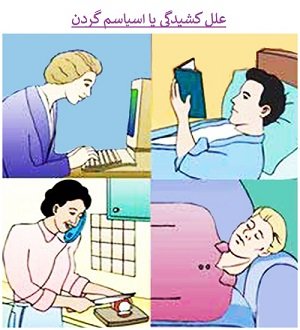

1-کشیدگی عضلات گردن

وقتی فشار زیادی به گردن خود وارد میکنید (یکی از علل شایع آن قرار دادن سر و گردن در یک وضعیت نامناسب به مدت طولانی است) عضلات و لیگامان های اطراف ستون مهره ای گردن شما تحت کشش زیادی قرار میگیرد و به دنبال آن ممکن است پارگی های میکروسکوپی در آنها ایجاد شود. بدنبال آن در این بافت ها تورم و درد ایجاد میشود که شما آن را به صورت درد و خشکی گردن احساس میکنید.

این محدودیت حرکت قدری به علت درد و قدری به علت انقباض عضلات اطراف ستون مهره است که خارج از اراده شما صورت میگیرد و به آن اسپاسم هم میگویند. مهمترین علائم کشیدگی و رگ به رگ شدن گردن عبارتند از : درد بخصوص در پشت گردن که با حرکت گردن شدیدتر میشود، دردی که بعد از دوسه روز از ضربه ایجاد میشود نه بلافاصله بعد از آن، درد در بالای شانه، سردرد در پشت سر، افزایش تحریک پذیری و خستگی. بدخوابی و اختلال تمرکز، گزگز در اندام فوقانی، خشکی در حرکات گردن، ضعف در حرکات اندام فوقانی. این نوع درد معمولاً با چند روز استراحت و گرم کردن موضع خوب میشود.